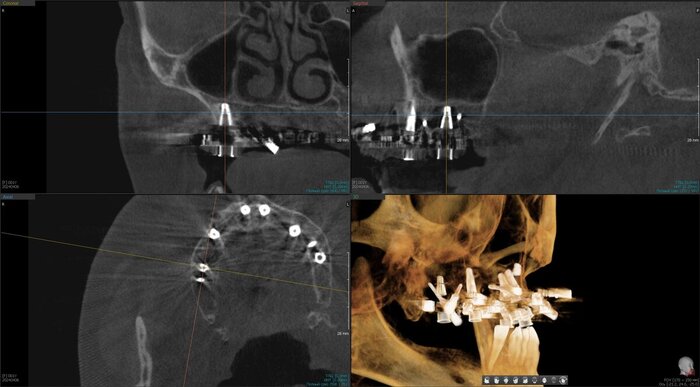

Получилось так, что сверху всего 8 зубов, по 4 с каждой стороны. Чёрная точка (которую вы точно увидите, скос эмали на зубе 1.1) - конструктивные особенности, всё это будет закрыто пломбировочным материалом. Зуб 1.1 - дополнительный имлантат, который потом планируем убрать. Он нужен лишь для усиления, ибо торк полноценный был получен только на одном из остальных 6-ти установленных.

Так же важный момент - верхний протез соприкасается с нижним только в точках полученного торка (их всего 2), остальное "на весу" и жевать не способно.

не играет решающей роли ,сколько дней от имплантации до постановки протеза прошло. Важен торк (усилие) и пассивность конструкции. То есть протез на имплантаты должен усаживаться без боли, пассивно.

И будет успех.